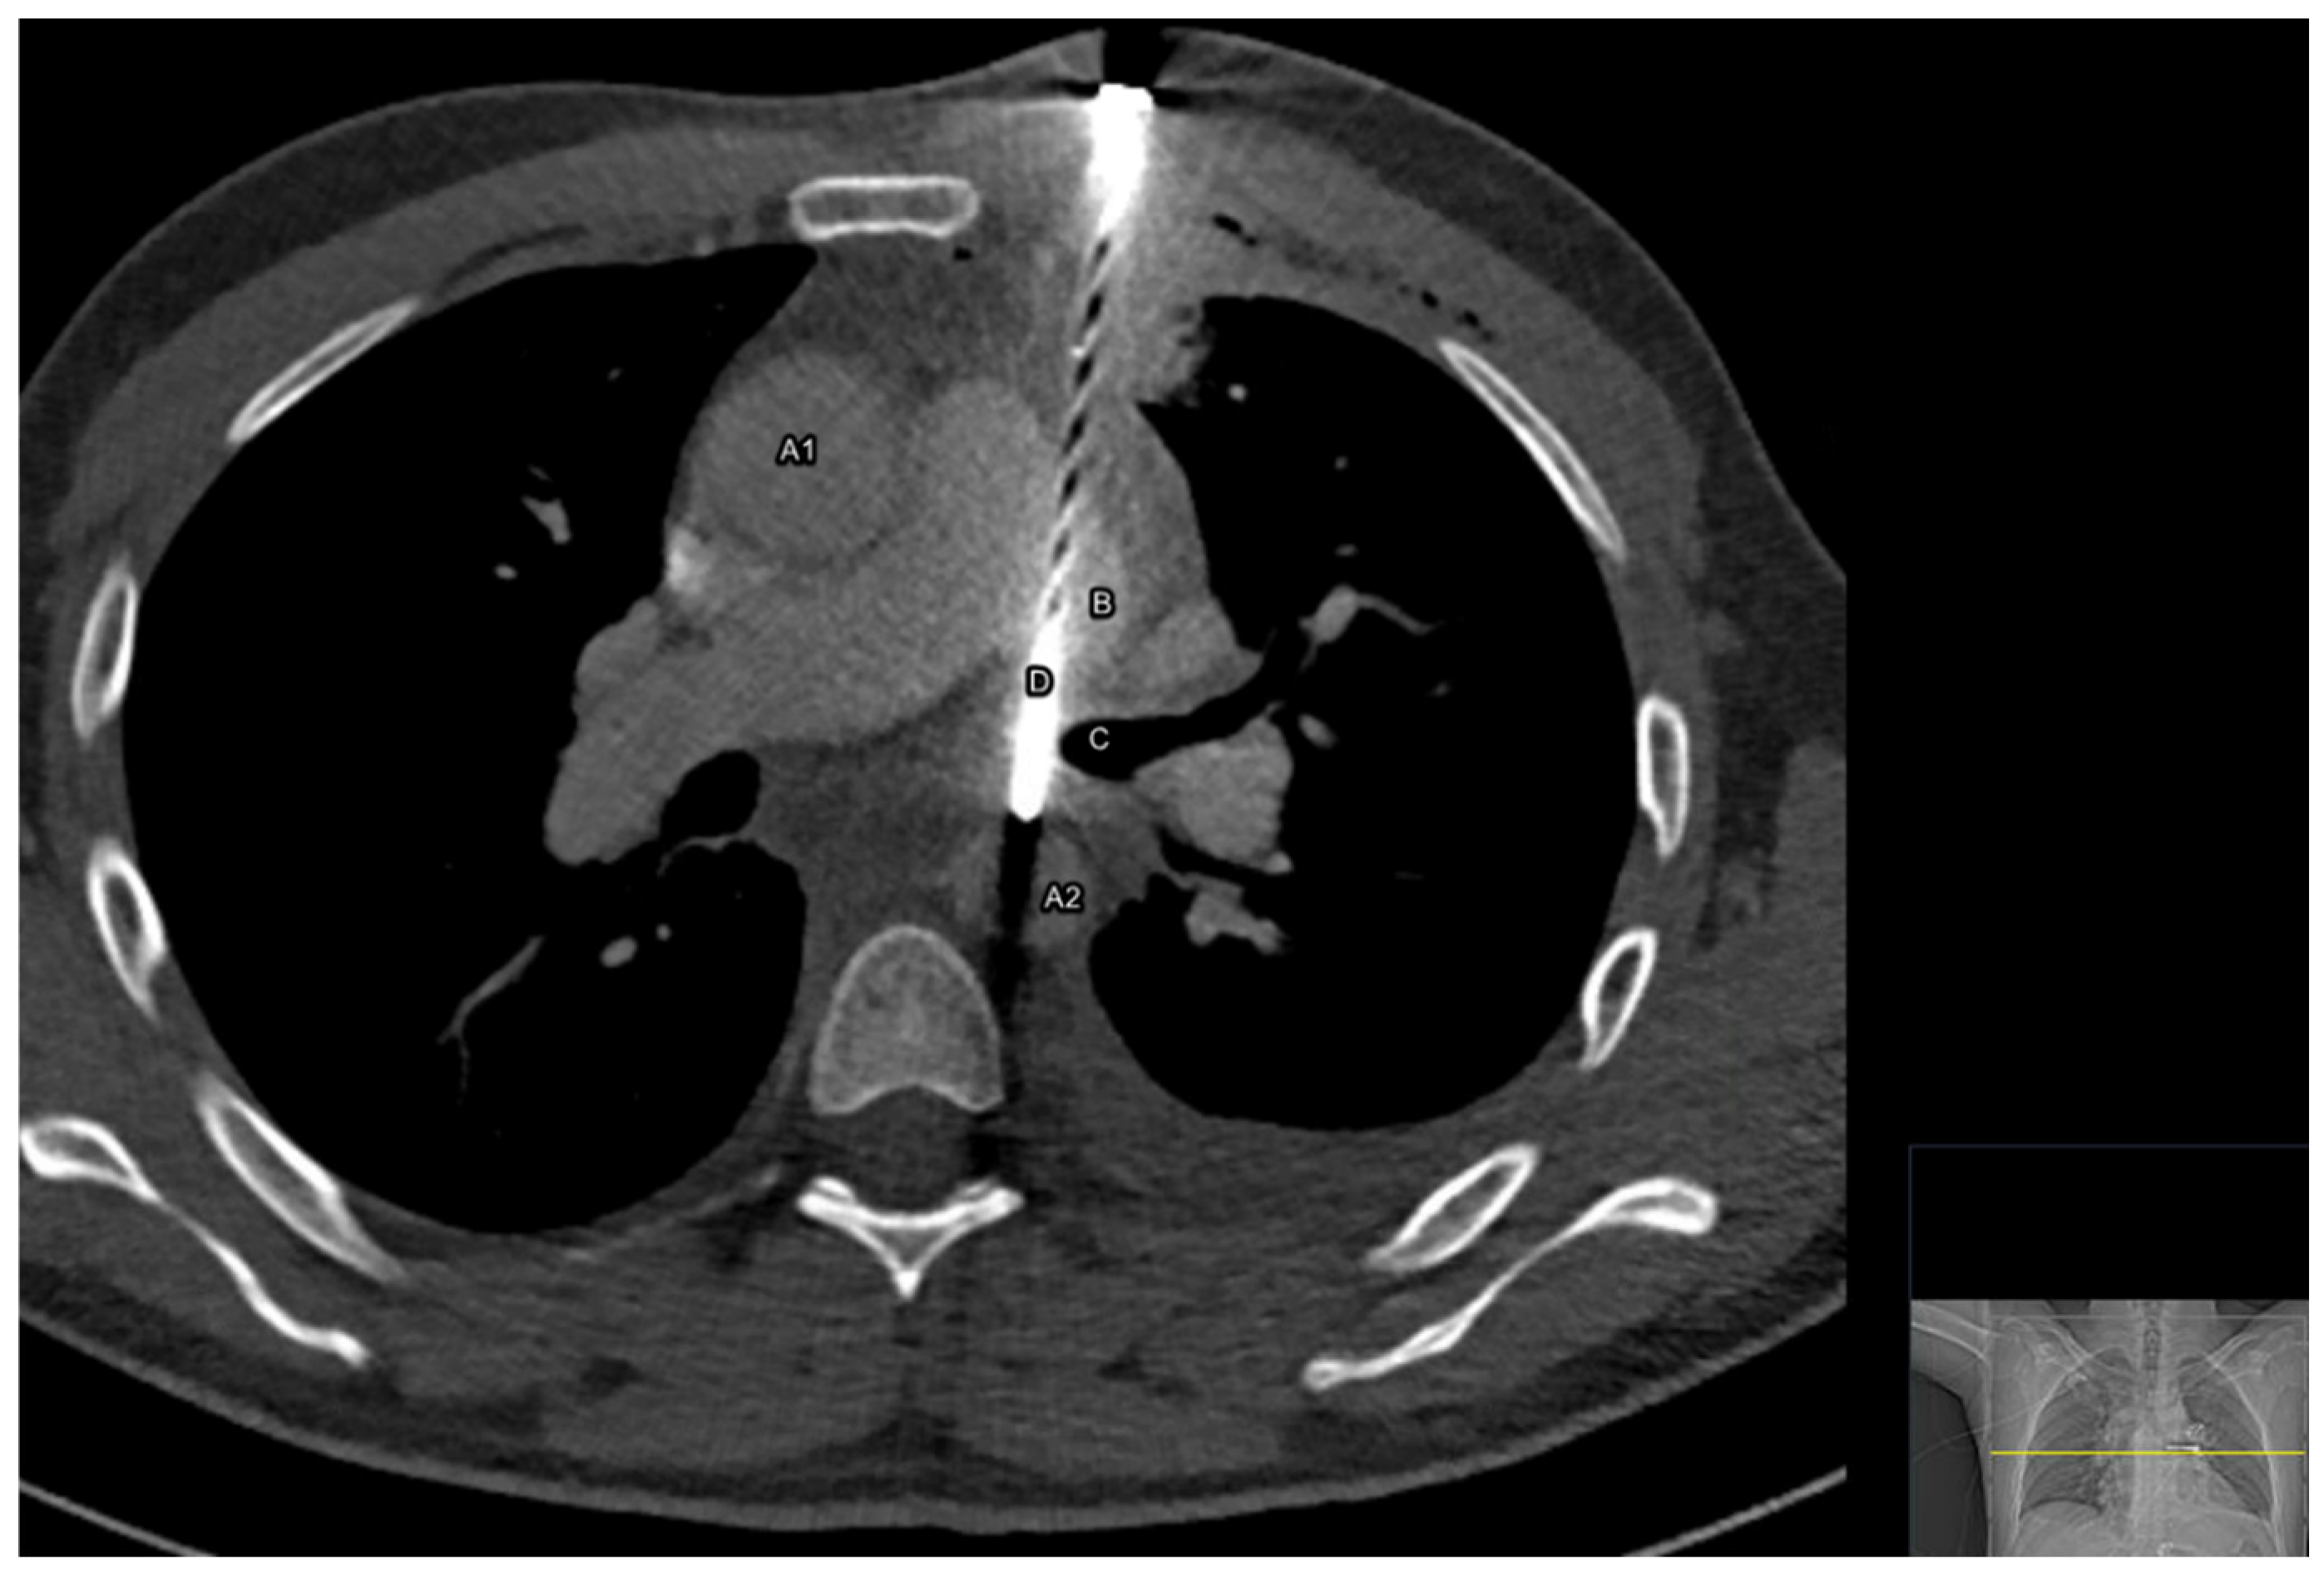

The CT scan showed an unexpected foreign body with the radiographic appearance of a nail of 12.6 cm, with the entrance at the left parasternal between costa two and three, penetrating part of the left pulmonary upper lobe, the left pulmonary artery, and the left main bronchus and with its tip positioned in the descending aorta. Small amounts of fluid were visible along the ascending aorta, in the pericardial sac and in the left pleural space, accompanied by a small pneumothorax at the top of the left lung.

Figure 1. Transverse image of the chest CT scan showing a 12.6 cm long nail and its trajectory through the thorax and vital structures. A1 = ascending aorta, A2 = descending aorta, B = left pulmonary artery, C = left main bronchus, and D = nail (12.6 cm).